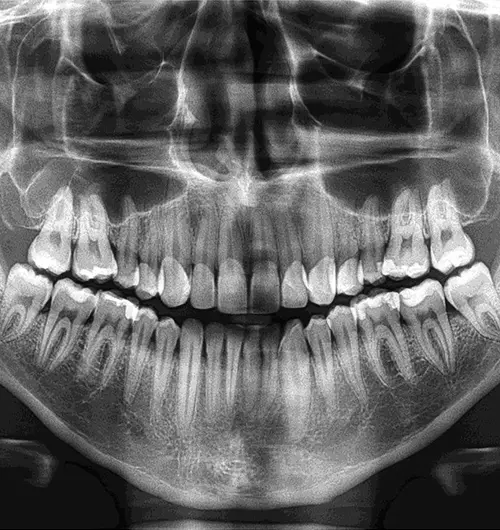

Panoramic X RAY

It’s an advanced X-ray technology used to review jaws, teeth, and nearby bone clearly &

completely. This full mouth image helps identify jaw problems, affected teeth & complete oral

health, guiding with implants, orthodontics & advanced solutions.